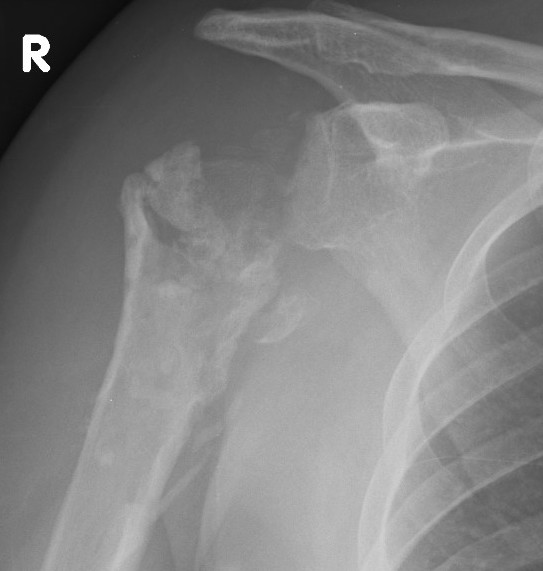

Superior rotator cuff failure

Cause

Humerus overstuffing

Glenoid superior tilting

Failed rotator cuff repair

aTSA overstuffing

Prevention

Must ensure don't leave humeral head proud

- restore Shenton's line

Issue

Results in eccentric loading of the superior aspect of glenoid component & loosening

- "rocking horse glenoid"

Diagnosis

Superior migration of humeral head on xray

Shoulder Hemiarthroplasty Rotator Cuff FailureTSR Superior EscapeaTSA failed cuffTSR Failed Rotator CUff